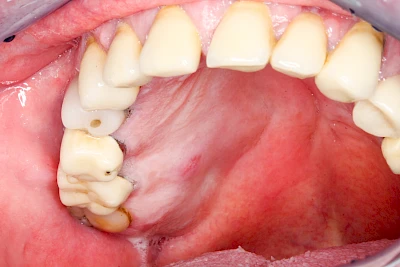

Sonderform: Fistel

Bei einer Fistel hat sich meist eine Entzündung (manchmal auch Erreger selbst) z. B. aufgrund von Karies oder aufgrund eines Unfalls über den Zahnnerv und die Wurzelspitze (Apex) in den umliegenden Knochen ausgebreitet (apikale Parodontitis) und schnell einen Weg durch den umgebenden Knochen und die aufliegende Schleimhaut in die Mundhöhle gebahnt.

Fisteln sind in der Regel nicht schmerzhaft und fallen häufig als kleine Öffnung weiter entfernt vom Zahnfleisch nahe der Umschlagfalte auf. Aus der Fistelöffnung entleert sich spontan gelbliches Sekret (Eiter) oder es lässt sich mit dem Finger ausstreichen. Manchmal beschreiben die betroffenen Menschen immer wieder einen komischen Geschmack im Mund.

Im fortgeschrittenen Stadium kann die Schleimhaut sich weiter zurückgezogen haben und die Wurzelspitze sichtbar sein. In der Regel treten bei Fisteln keine Schwellungen auf, weil sich die Entzündung nicht im Gewebe ausbreitet.